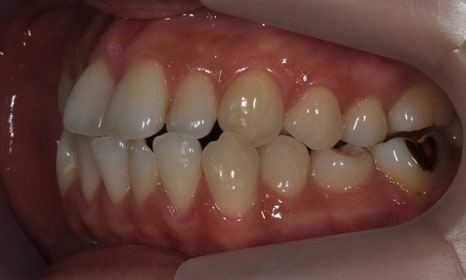

다음 케이스 역시 위 아래 치아의 중심선 차이가 있으며, 덧니 및 반대교합이 관찰되었습니다. 위 치아의 중심선도 얼굴의 중심선과 일치하지 않고 우측(사진 상 왼쪽)으로 틀어져 있었습니다. 본 환자는 발치를 하지 않고 치아를 뒤로 이동시켜서 치아의 중심선도 맞추고 얼굴의 중심선과도 맞추었습니다.

2020.1

교정 마무리 후 위 치아의 중심선은 얼굴의 중심선과 일치하였으며, 위 아래 치아의 중심선도 일치하였습니다.

2022.7